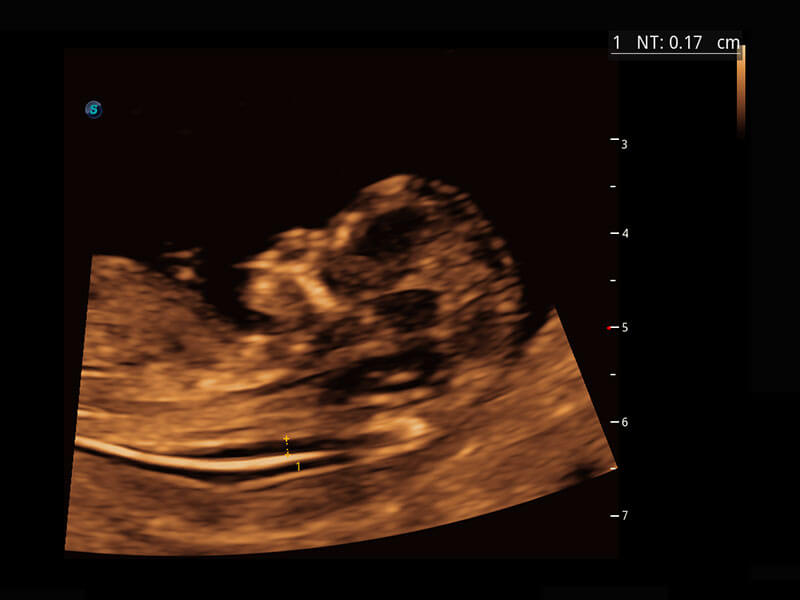

早孕筛查

P60在胎儿早孕期超声筛查中为您带来优异的图像质量。

• 早孕-胎心

• 高分辨率容积成像-早孕胎儿